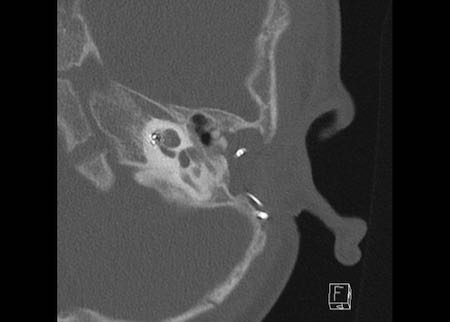

Ca lâm sàng 1

Các hình ảnh cho thấy tai trái của cùng bệnh nhân, nơi thính lực bị suy giảm.

Điện cực không được đưa vào đủ sâu, năm kênh nằm trong hòm nhĩ và đầu điện cực không đạt tới đỉnh ốc tai.